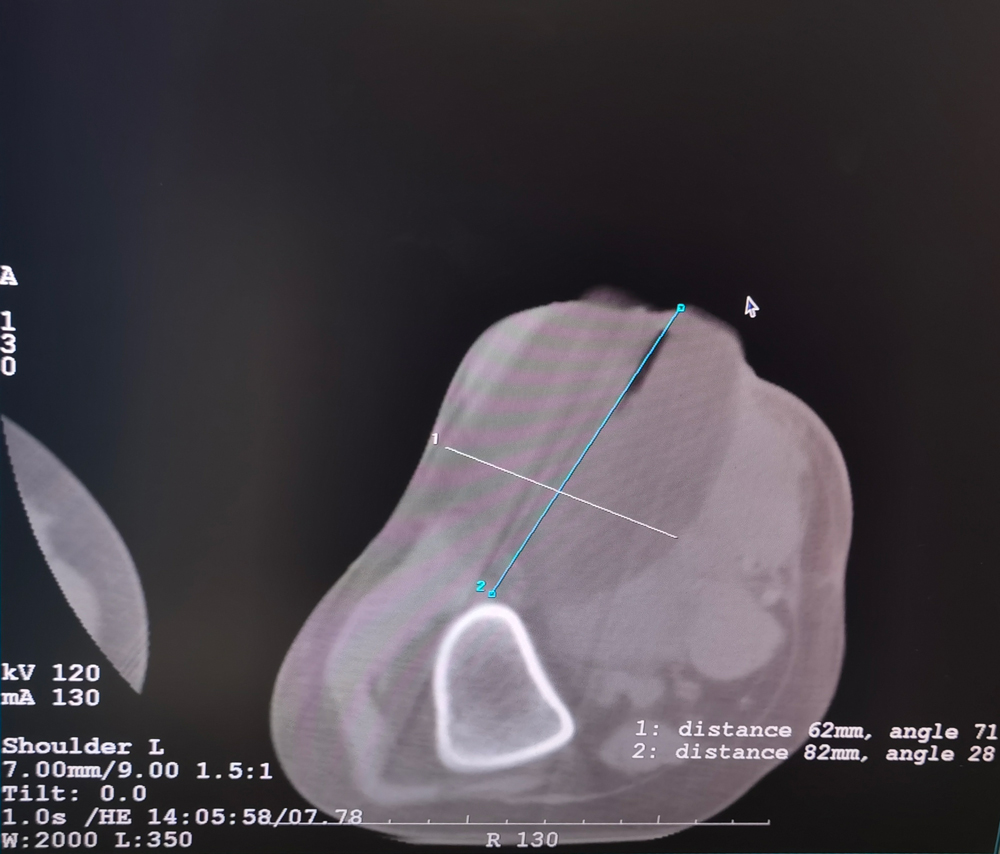

女,42歲,復(fù)發(fā)性脂肪瘤,病灶位于右側(cè)膝關(guān)節(jié),直徑大小13cm。采用雙針?lè)桨?,共進(jìn)行6個(gè)凍融循環(huán),最大冰球直徑達(dá)8.2cm,術(shù)中多方位治療全面覆蓋病灶范圍。患者術(shù)后狀況良好。